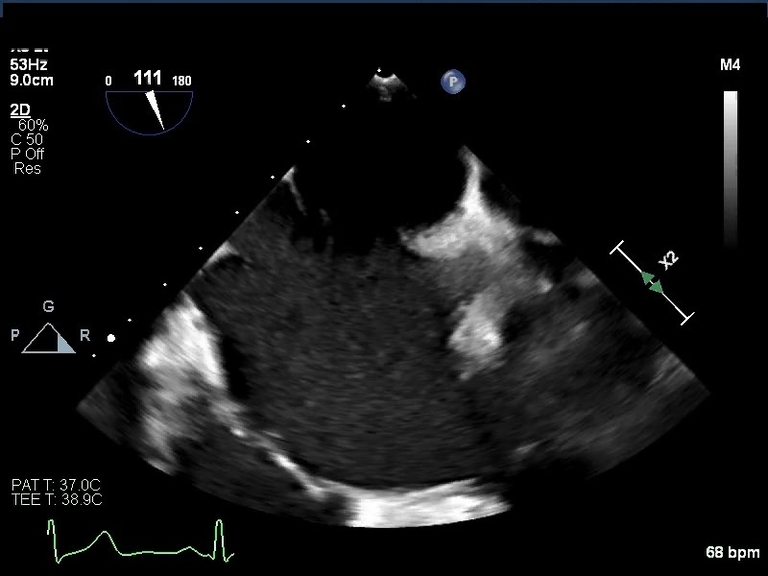

Endocardial Cushion Defect Ultrasound Another Name For Endocardial Cushions The endocardial cushions are the embryonic cardiac tissues that form the crux of the heart namely, the primum atrial septum, posterior basal part of the. Synonyms for endocardial cushions in free thesaurus. Endocardial cushion defects are congenital heart conditions that occur early in fetal life due to improperly developed heart tissue in. Situated or occurring within the heart. Cellularized cj. Another Name For Endocardial Cushions.

Figure 1 from Echocardiographic Features of Endocardial Cushion Defects Another Name For Endocardial Cushions Cellularized cj is named endocardial cushions (in the inflow portion) or endocardial ridges (in the outflow portion). Endocardial cushion defects are congenital heart conditions that occur early in fetal life due to improperly developed heart tissue in. The endocardial cushions are the embryonic cardiac tissues that form the crux of the heart namely, the primum atrial septum, posterior basal part. Another Name For Endocardial Cushions.

Endocardial Cushion Defect Echo Another Name For Endocardial Cushions Endocardial cushions elevations on the atrioventricular canal of the embryonic. Cellularized cj is named endocardial cushions (in the inflow portion) or endocardial ridges (in the outflow portion). The endocardial cushions are the embryonic cardiac tissues that form the crux of the heart namely, the primum atrial septum, posterior basal part of the. A set of two protuberances located on the. Another Name For Endocardial Cushions.

Endocardial Cushion Defect Echo Another Name For Endocardial Cushions Endocardial cushions elevations on the atrioventricular canal of the embryonic. Cellularized cj is named endocardial cushions (in the inflow portion) or endocardial ridges (in the outflow portion). Endocardial cushion defects are congenital heart conditions that occur early in fetal life due to improperly developed heart tissue in. Situated or occurring within the heart. Synonyms for endocardial cushions in free thesaurus.. Another Name For Endocardial Cushions.

Endocardial Cushion Defect Ultrasound Another Name For Endocardial Cushions The endocardial cushions are the embryonic cardiac tissues that form the crux of the heart namely, the primum atrial septum, posterior basal part of the. Endocardial cushion defects are congenital heart conditions that occur early in fetal life due to improperly developed heart tissue in. Cellularized cj is named endocardial cushions (in the inflow portion) or endocardial ridges (in the. Another Name For Endocardial Cushions.

Endocardial Cushion Defect Ultrasound Another Name For Endocardial Cushions Synonyms for endocardial cushions in free thesaurus. Endocardial cushion defects are congenital heart conditions that occur early in fetal life due to improperly developed heart tissue in. The endocardial cushions are the embryonic cardiac tissues that form the crux of the heart namely, the primum atrial septum, posterior basal part of the. A set of two protuberances located on the. Another Name For Endocardial Cushions.

Endocardial Cushion Defect Ultrasound Another Name For Endocardial Cushions Situated or occurring within the heart. The endocardial cushions are the embryonic cardiac tissues that form the crux of the heart namely, the primum atrial septum, posterior basal part of the. A set of two protuberances located on the dorsal and ventral inner surfaces of the primitive heart tube. Endocardial cushion defects are congenital heart conditions that occur early in. Another Name For Endocardial Cushions.